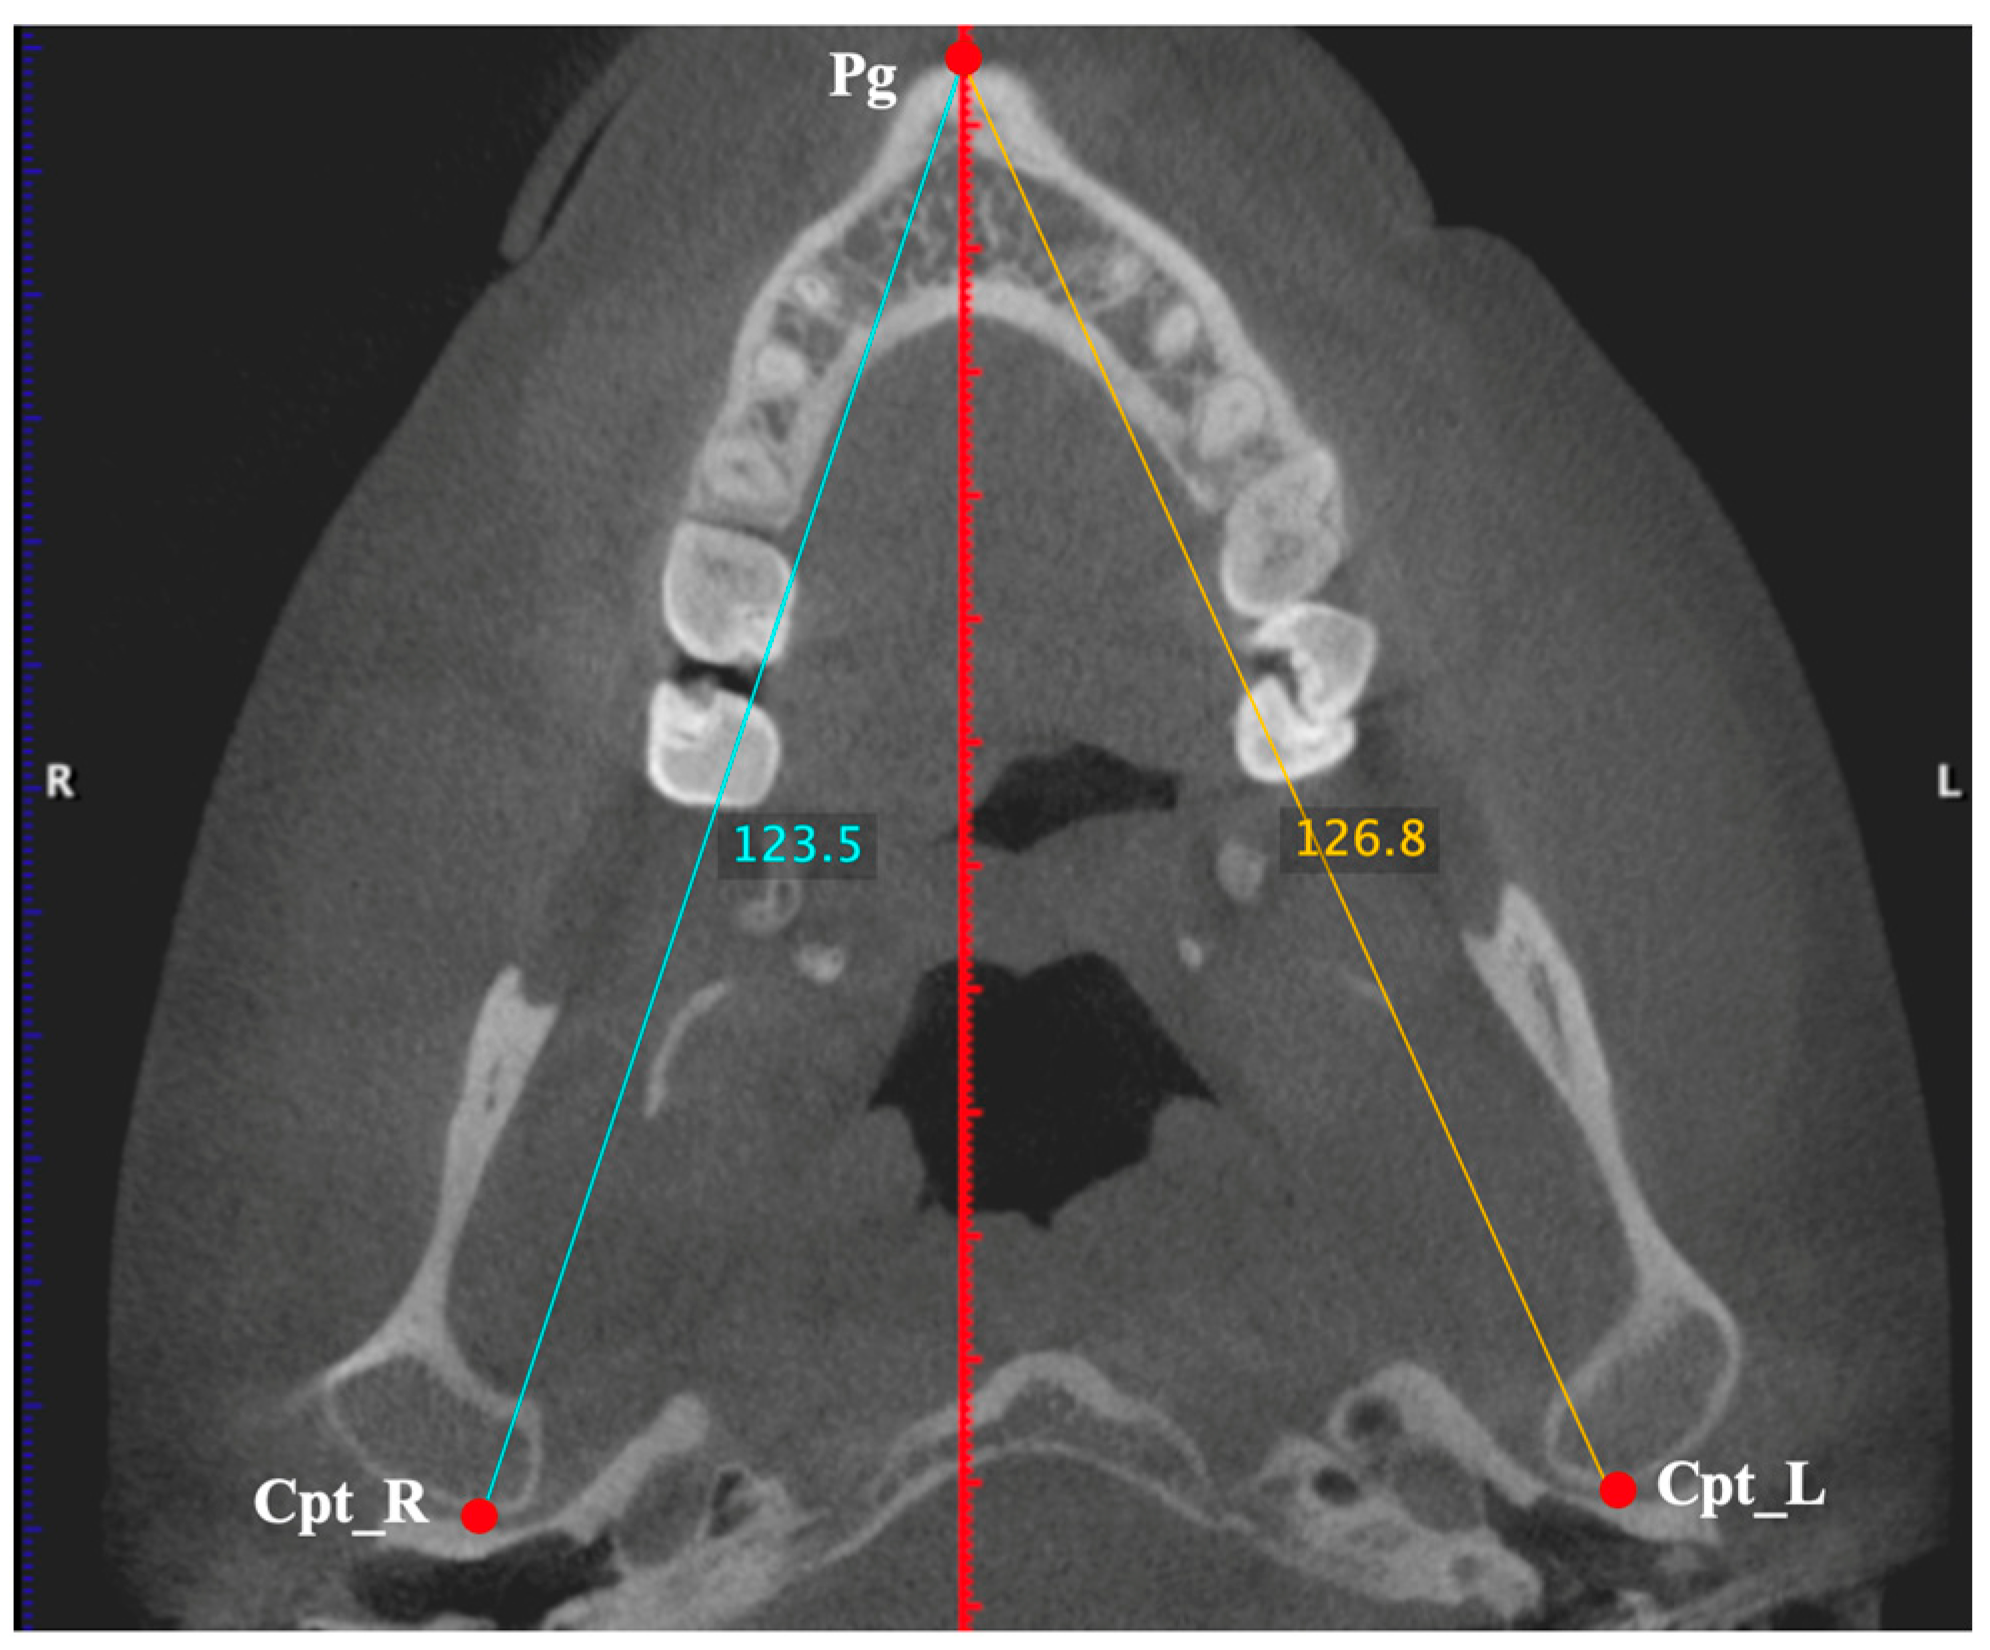

- Hemimandible length: From point Cpt to point Pg. Measurement taken on the right and left sides (Figure 3);

| Cpt | Condyle-posterior | Most posterior point of the mandibular condyle |

| Pg | Pogonion | Most anterior point of the outline of the mandibular symphysis |